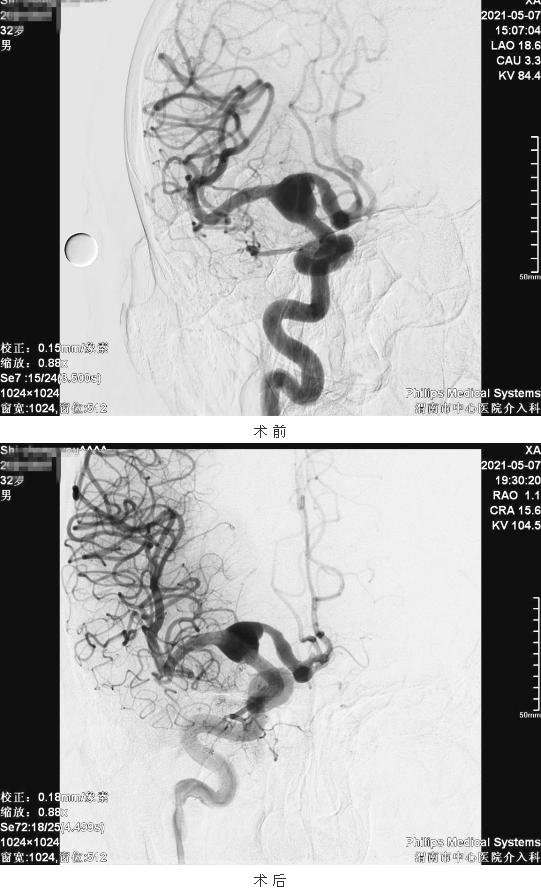

患者男性,32岁,晨起时突发左侧肢体麻木,伴左上肢无力,就诊于市中心医院脑血管病专科门诊。急诊以“急性脑梗塞、颅内动脉瘤”收住市中心医院。入院后行DSA全脑血管造影术提示:右侧颈内动脉末端分叉处巨大夹层动脉瘤。该患者颅内巨大夹层动脉瘤,属于复杂性颅内动脉瘤,累及右侧颈内动脉末端、右侧大脑中动脉、右侧大脑前动脉等主干血管,瘤体较大,不规则,无明显瘤颈,且患者合并高血压等危险因素,动脉瘤破裂风险较高,破裂后的致死率高,故必须进行积极手术治疗。这是选择行颅内动脉瘤介入治疗的指征。但此类颅内巨大夹层动脉瘤采用以往常规的支架辅助动脉瘤栓塞或者其他介入治疗方法,并发症发生率高,术后复发率很高,无法达到预期效果。

术中经T-track微导管送入Tubridge5.0mm×45mm密网支架一枚,完全覆盖动脉瘤,即刻造影显示动脉瘤瘤腔内造影剂滞留明显,载瘤动脉通畅,顺利完成手术。